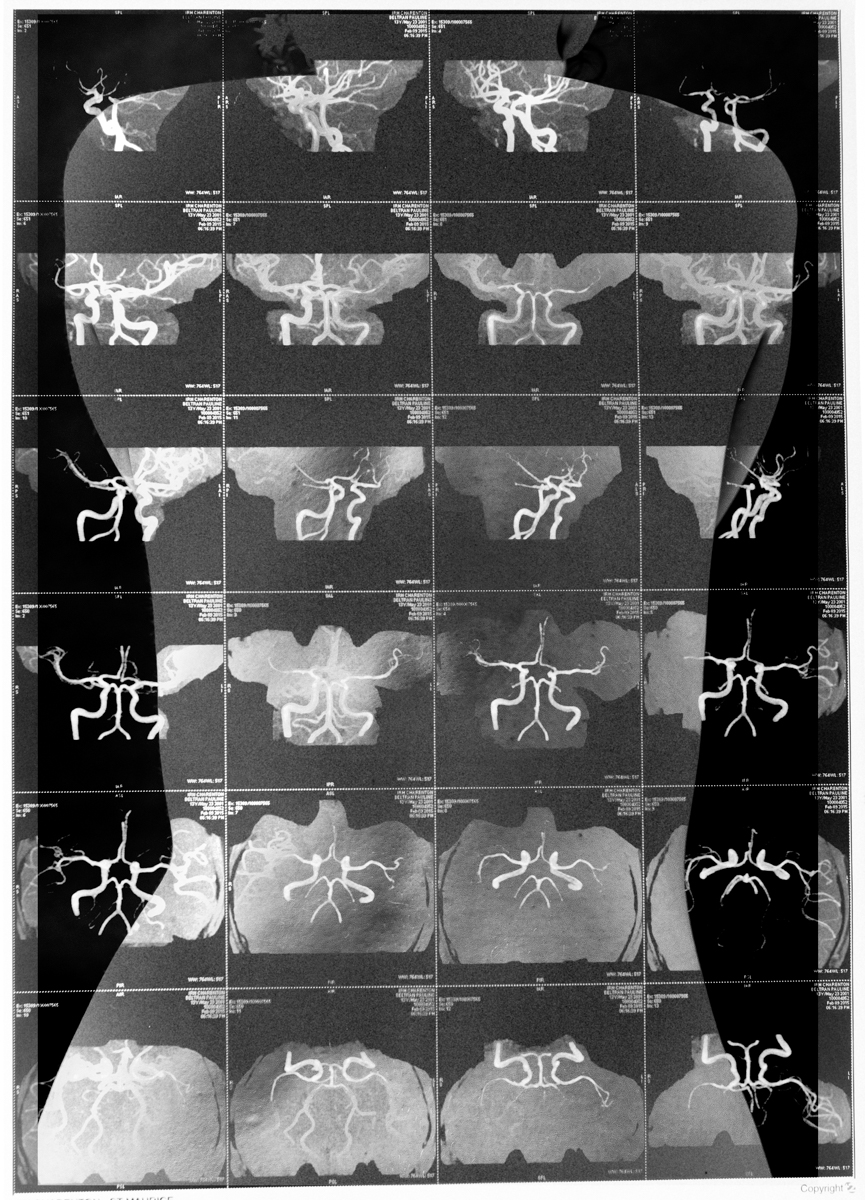

SURFACES SENSIBLES — À la frontière de l'autoportrait, "Surfaces sensibles" retranscrit une partie de ma réalité et brouille les limites entre l'intime anatomique et l'émotionnel.

La science produit les images les plus concrètes et les plus neutres pour illustrer les affects. Pourtant, par leur froideur et leur distance, elles sont les moins aptes à témoigner des émotions. Chaque radiographie, scanner, IRM correspond à une douleur ou à un mal-être spécifique.

Depuis peu, ces images ne sont plus seulement des réminiscences de douleurs passées, mais également des matériaux bruts inspirants pour ma pratique photographique. À partir des radios originelles, j'ai utilisé plusieurs techniques telles que la superposition et le tirage argentique dans le but de me rapprocher d'une perception alternative de ce corps irradié.